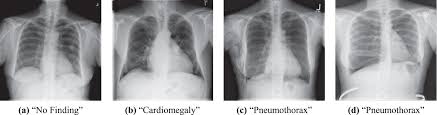

Comparison Of Deep Learning Approaches For Multi Label Chest X Ray Classification Scientific Reports

Comparison Of Deep Learning Approaches For Multi Label Chest X Ray Classification Scientific Reports from media.springernature.com

The condition spans all age groups, and ems providers should, therefore, maintain a high index of suspicion for pneumothorax for any patient with a. Tap on/off image to show/hide findings. However, treatment is reliant on timely review of radiographs. If you cannot diagnose a tension pneumothorax at medical finals you won't find an examiner who will defend you. A normal or raised paco 2 is concerning as it indicates that the patient is tiring and failing to ventilate effectively. Ipsilateral pleural line with reduc ed/absent lung markings (i.e., increased transparency) abrupt change in radiolucency; Pneumothoraces may be small or very large. In this video, you'll learn how to identify when radiological pleura is abnormal and the key signs to look out for when trying to diagnose a pneumothorax.

Patients with a larger pneumothorax may have decreased movement of the chest wall, a positive coin test result, diminished fremitus, or decreased to absent breath sounds on the affected side. Most individuals with primary spontaneous pneumothorax (psp) have unrecognized lung disease; If a hemothorax occurs concurrently with a pneumothorax it is then termed a hemopneumothorax. The video is an effort to revisit the pneumothorax. Radiographic findings of 2.5 cm air space are equivalent to a 30% pneumothorax. Please see disclaimer on my website www.academyofprofessionals.com Ipsilateral pleural line with reduc ed/absent lung markings (i.e., increased transparency) abrupt change in radiolucency; Schematic illustration of the radiographic findings and differences between pneumothorax and artifacts related to skinfolds. 6 10 supportive findings of pneumothorax. Distracting injuries such as fractures or peritonitis were also noted. Tap on/off image to show/hide findings. Clinical signs of a tension pneumothorax in the ventilated patient are comparably rapid, with arterial and mixed venous peripheral capillary oxygen saturation immediately decreasing 5. A pneumothorax refers to the presence of gas or air in the pleural space.